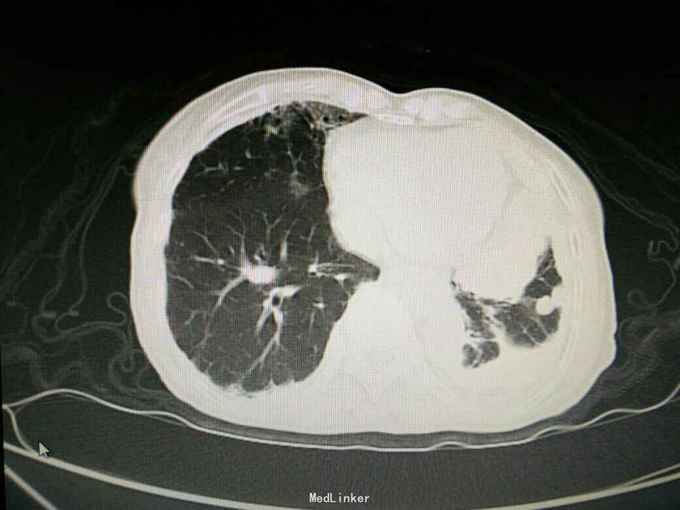

患者陈某某,女,69岁。 主诉:反复咳嗽咳痰1年余,加重伴气促1月。 病史:1年前出现咳嗽咳痰,阵发性,少量白痰,无发热,无盗汗消瘦,无胸闷胸痛,未予重视。1月余前出现咳嗽咳痰加重,伴气促,活动后明显,无夜间阵发性呼吸困难,当地医院胸片示左侧胸膜多发肿块,两侧胸膜增厚钙化,随后至我院就诊。 既往史: 有石棉接触史20余年,40年前行输卵管结扎术,26年前行阑尾切除术,否认其他疾病史,否认烟酒史。

查体:神志清,精神可,生命体征平稳。两肺呼吸音粗,未闻及干湿性啰音。 辅查: 血气分析:PH7.43, 二氧化碳分压43mmHg, 氧分压77mmHg, 氧饱和度95%。 血常规:WBC7.5x10∧9/L, NE77.8%, Hb132g/L, plt231x10∧9/L。 尿常规,粪便常规,凝血功能,肿瘤标志物,CRP, 免疫功能,肝肾功能电解质无明显异常。 痰培养,痰找抗酸杆菌阴性。 心电图无明显异常。 心脏彩超:主动脉瓣局部退行性变,左室舒张功能减退,轻度肺高压。 腹部B超无异常。 胸部增强CT:双侧多发胸膜斑,左侧胸膜弥漫结节状及团块形成,考虑石棉肺伴左侧胸膜继发性恶性间皮瘤可能。

入院诊断:左侧胸膜肿物:胸膜间皮瘤? 诊治经过:予对症支持治疗,行CT引导下胸膜活检 病理:结合免疫组化和临床病史,符合恶性间皮瘤。 治疗:患者明确诊断后予化疗前预处理,择期行培美曲塞+铂类化疗

胸膜间皮瘤是原发于胸膜间皮组织或胸膜下间质组织的一种少见肿瘤,可分为局限型和弥漫型,前者可为良性或低度恶性,后者均为高度恶性。 弥漫型间皮瘤大多与石棉接触有关,局限型则与石棉接触无关。 弥漫型胸膜间皮瘤多无手术机会。有主张胸膜切除加化疗和或放疗,可延长生存期。